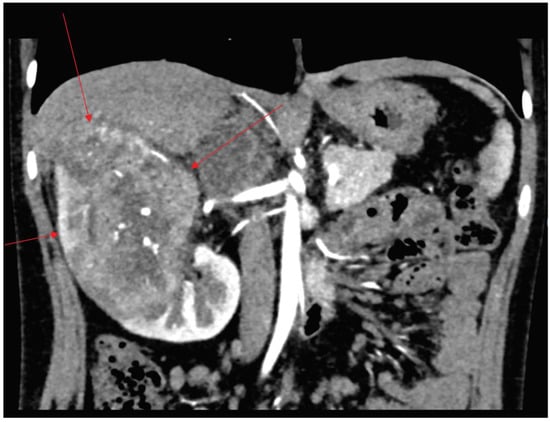

| Diagnosis | Right lung: 5 nodules (5 × 5 mm) Left lung: 2 nodules (4 × 5 mm) Left hilus: 2 lymph nodes (max size 16 mm). | CT and MRI: a tumour in the right kidney (81 × 81 × 104 mm), renal vein infiltration, tumour capsule rupture, right hepatic lobe infiltration, suspected metastases to the right adrenal gland and the peritoneum. ileocecal lymph node (15 × 5 mm) | confirmed active disease process in the same places as in CT/MRI |